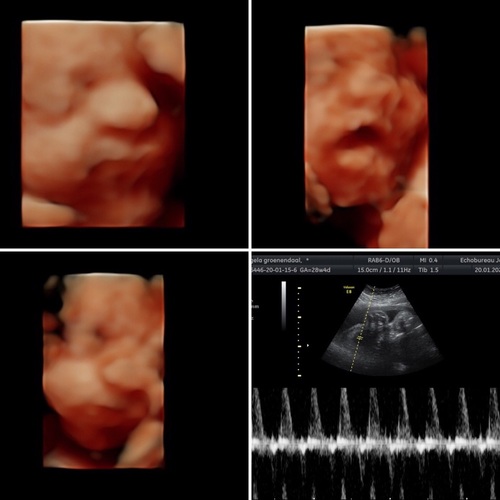

Ja, hier ook goede ervaring. Pretecho gehad met 15.3 voor het geslacht. Dit klopte en hij nam ook gelijk de tijd om naar zn voetjes, lip en hoofdje te kijken (hij maakt voor zn werk ook medische echo's). Daarna heeft hij echt een paar minuten de echo erop gehad, puur om te kijken naar wat de baby aan het doen was. Heel leuk!

Ik ben met 28 weken bij hem geweest voor een 4D-echo. De kleine lag al ingedaald en met haar hoofdje tegen de baarmoederwand, daardoor geen fantastisch mooie foto. Maar wel een hele leuke echo gehad. Het is echt een hele kundige vriendelijke man die plezier heeft in zijn werk. Inderdaad is de praktijk oud en niet modern, maar dat is ook het enige wat erop aan te merken is.